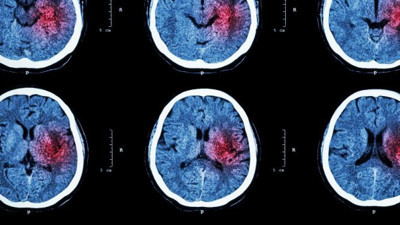

Riski yüzde 60 arttırıyor. Bu ilaçları kullananlar dikkat Adana Şehir Eğitim ve Araştırma Hastanesi İnme Merkezi Sorumlusu Nöroloji Uzmanı Prof. Dr. Zülfikar Arlıer, beyin kanamasının gelişen tıp teknolojisi ile çoğu zaman ameliyata dahi gerek kalmadan önlenebildiğini kaydetti. Kan sulandırıcı kullanan hastalarda beyin kanamalarının daha ağır seyredebileceğine dikkat çeken Arlıer, "Kan sulandırıcı kullanan hastalarda beyne yavaş yavaş sızıntı olup bazen 1 yıl sonra bile çok büyük, beyne baskı yapan, komaya sokan durumlar oluşabilir, ölümcül netice verebilir" dedi.

Beyin kanaması yaşı 6’ya kadar düştü Türkiye’de geçtiğimiz yıl yaklaşık 7 bin beyin kanaması vakası görüldüğünü belirten Beyin ve Sinir Cerrahı Doç. Dr. Ali Yılmaz, "Genç yaştaki hastalarda beyin baloncuğu görülme oranında artış var. 6 yaşında dahi beyin baloncuğu gördüğümüz çocuklar var. Beyin damarlarında görülen baloncuk tedavi edilmezse kanamaya yol açabilir" dedi.

Beyin kanamasından nasıl korunuruz? Uz. Dr. Rodi Sarı Polat, beyin kanamaları ve korunma yöntemlerine ilişkin yaptığı açıklamada, beyin kanamasına işaret edebilen bazı belirtilerin görüldüğünde vakit kaybetmeden hastaneye başvurulması gerektiğini söyledi.